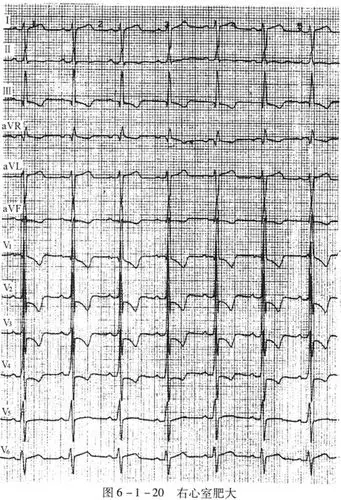

图6-1-20右心室肥大

心电图示:窦性心律,不正常心电图,右心室肥大,右心房扩大.

右心室肥厚心电图图谱,心电图诊断教学图解,临床动态正常异常心电图

心室肥大的心电图表现